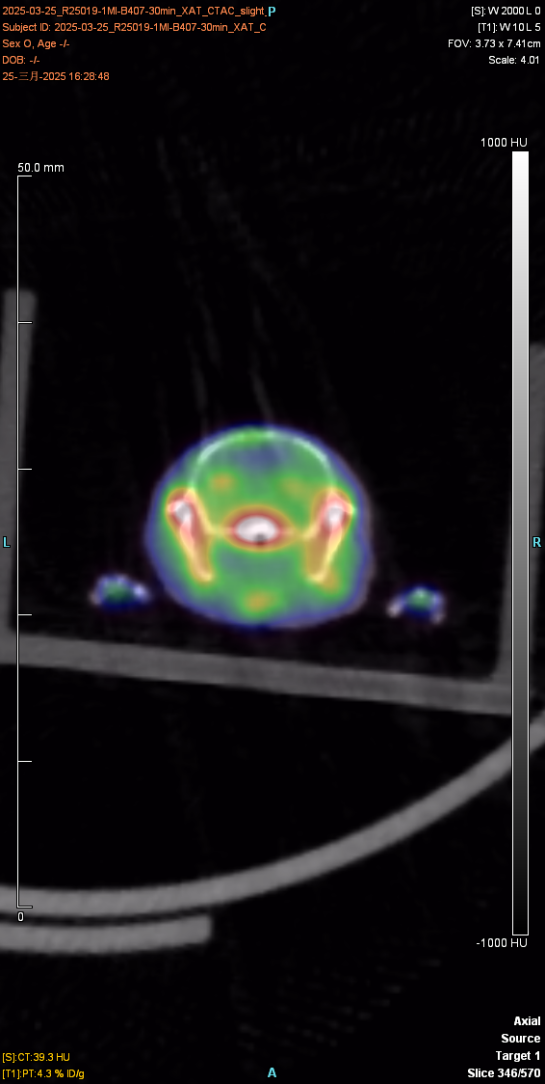

下(xià)圖為(wèi)30min顯像圖像